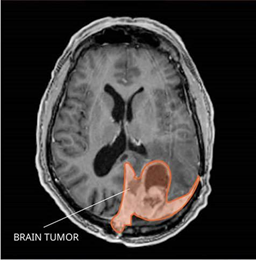

Refer to caption

Figure 1: Brain Tumor (https://www.cancer.gov/rare-brain-spine-tumor/tumors/meningioma)